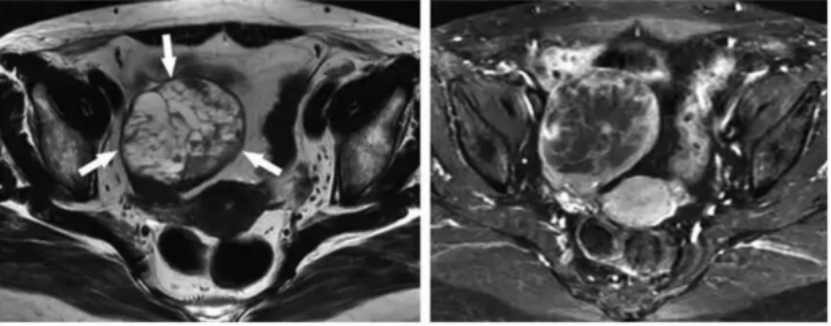

盆腔内见巨大多房囊实性包块,囊液内信号不一,部分囊液呈T1WI低信号、T2WI及T2-FS呈高信号,部分囊液呈T1WI等信号、T2WI及T2-FS稍高信号,部分囊液T1WI稍高信号、T2WI及T2-FS均呈低信号(真空征),病灶内见分隔,实性成分位于分隔处、DWI无明显弥散受限,动态增强实性成分及分隔呈明显持续强化;右侧卵巢可见;盆腔少量积液。

诊断意见:左侧卵巢甲状腺肿可能。

SO多为单侧发生(约90%病例),呈边界清晰类圆形或分叶状肿块,以多房囊性结构为主,完全实性罕见,囊腔大小不一,囊壁多光滑、均匀,实性成分嵌插分布位于囊壁及分隔处;以下影像学特征对诊断有一定帮助①囊液:由于各分房内含碘甲状腺素及甲状腺球蛋白,具有很强X线衰减能力,故囊液密度增高,对应T2WI信号减低,研究显示CT值较高的囊性区域,T2WI信号往往呈极低信号(低于相邻骨骼肌),被称为“真空征”,这可能由于囊内含大量胶冻样物质,这些物质多由大量纤维素构成,导致氢含量少所致,在影像学上具有辨识度;部分可见囊内出血。②钙化:与甲状腺相似,卵巢甲状腺肿的实性区域容易钙化,54-60%的病例囊壁或分隔常出现斑点状、线条状、蛋壳样或弧形钙化;③明显强化的实性成分及分隔:实性成分中含有甲状腺组织和血管丰富的不成熟纤维基质,强化显著,增强幅度常高于子宫肌层,呈珍珠瘤样、花边状强化,DWI无明显弥散受限;④脂肪成分:提示畸胎瘤来源的重要线索。⑤肿瘤边缘不规则,呈侵袭样生长时提示恶变(MSO),MS0可通过种植、淋巴道、血性转移;转移或种植病灶的特征与原发肿瘤完全不同,多为固体结节。